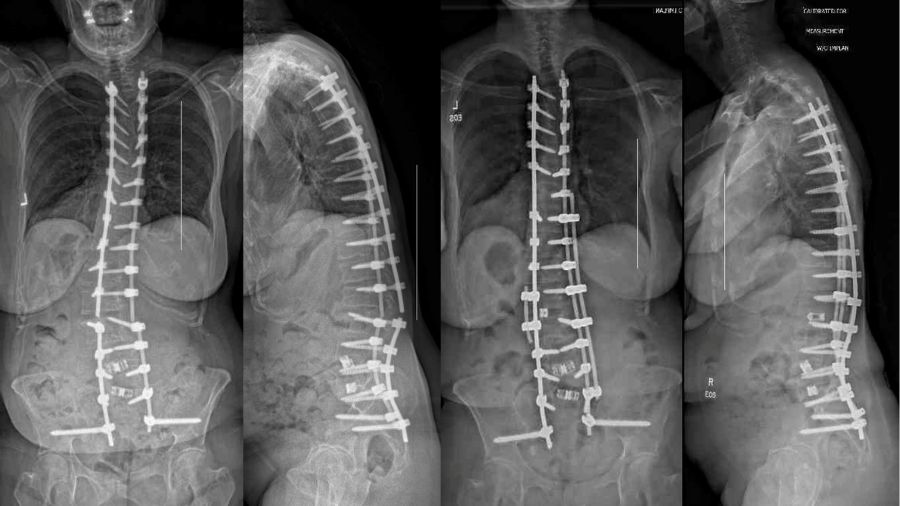

AO Spine Knowledge Forum Deformity has launched a new study exploring and comparing the durability of supplementary rod constructs—SuppleMentAry Rod Technique (SMART)—for long-segment posterior instrumented spinal fusion procedures. The landmark multinational retrospective study investigates the incidence, timing, risk factors, and management of rod fractures in deformity spine surgery. This collaborative effort aims to provide critical insights into one of the most common and challenging complications in spinal deformity corrections, potentially influencing surgical practices.

The study will focus on comparing two commonly used instrumentation techniques: dual-rod constructs and supplementary rod constructs. "Dual-rod systems are the standard approach, providing stability and strength for spinal fusion," Principal investigator Justin Smith explains. "In contrast, supplementary rod constructs, which involve additional rods most often placed parallel to the primary rods, are increasingly employed to enhance mechanical durability in long-segment or high-stress spinal deformity cases."

The anticipated results are expected to highlight the mechanical advantages of supplementary rods in reducing the incidence of rod fractures. Additionally, the study will assess the impact of factors such as type of rod construct and pelvic fixation techniques on rod fracture rates and clinical outcomes.

"This study holds significant importance for the surgical community, " Co-Principal investigators Stephen Lewis and Michael Kelly added. "Rod fractures not only compromise the success of spinal deformity correction but also frequently necessitate revision surgeries, posing increased risks for patients." By identifying the key contributors to rod failure and understanding the role of supplementary rods in mitigating these risks, the findings will provide surgeons with evidence-based guidance to optimize surgical planning and patient care.